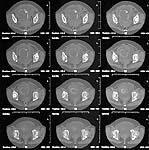

The CT showed a max displacement of 5 mm. Iliac and obturator views are obtained.

AP Pelvis

Iliac View

Obturator View

CT

After reviewing the Judet obliques and CT, I would tend toward nonoperative treatment. The maximum displacement is on the iliac oblique and the joint is certainly not perfectly congruent. However the femoral head seems nicely aligned to the acetabulum on all cuts of the CT and plain films.

I looked at the AP pelvis, Judet views, and CT you provided. This patient appears to meet all roof-arc criteria, and all ct-arc criteria (by my eval ~9 mm below vertex). The only question is late instability. I would follow the protocol of Tornetta et al for stress view under flouro (JBJS-BR 1999 January journal). If the femoral head stays congruent with the superior acetabular articular surface then non-operative management. (I think it will).